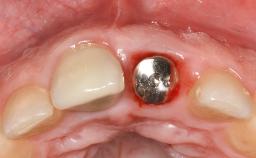

Treatment of Peri-Implantitis at a Zirconia Implant

Frank Schwarz, Ausra Ramanauskaite

Due to their promising clinical performance, zirconia implants have recently become popular alternatives to titanium implants, particularly for areas with high esthetic demands (Holländer and coworkers 2016; Roehling and coworkers 2016; Lorenz and coworkers 2019). However, regardless of the reported high survival and success rates, zirconia implants were affected by peri-implant diseases over the short observation period, suggesting the importance of treating peri-implant diseases at zirconia implants (Becker and coworkers 2017). In their case, Frank Schwarz and Ausra Ramanauskaite present 3-year results following mechanical debridement alongside Er:YAG laser monotherapy.